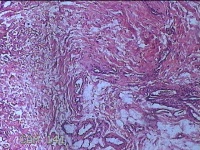

右侧髋部结节

性别

女

年龄

50岁

临床诊断

皮下结节

一般病史

发现右髋部结节1个月余。

标本名称

大体所见

灰白粉红色结节1.3x0.5x0.2cm一个,表面光滑,切开结节呈实性,切面灰白粉红色,质软。

图2

有的地方感觉像个血管瘤,未见明确恶性